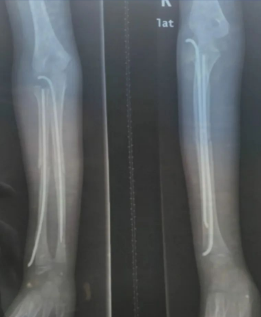

入院情况: 患儿龙**,男,10岁。因“右上肢疼痛伴活动受限1天于2023-08-17收住入院。

入院查体: 右上肢前臂活动严重受限,血液循环,皮肤局部肿胀、淤青,触痛明显,余未见异常。

门诊右尺挠骨DR示:右尺骨中段骨折

如下图示: